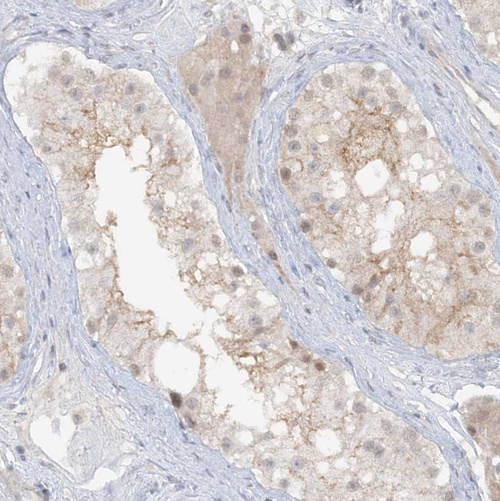

Immunohistochemical staining of human endometrium shows moderate positivity in apical membrane in glandular cells.